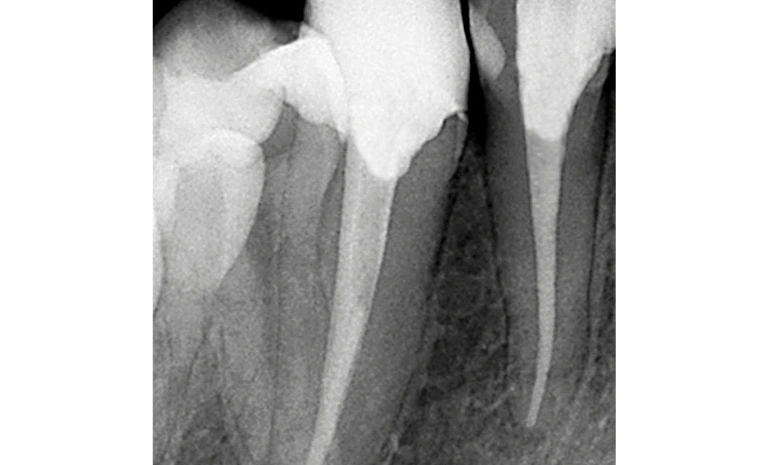

This common process removes infected pulp from inside your tooth. Modern methods make root canals as easy as regular fillings. In addition, this procedure relieves pain immediately.

Next, we gently take out the infected pulp. Afterward, we thoroughly clean all the root canals to remove all bacteria.

Once cleaned, we fill the empty space with a special material. This stops future infection and makes your tooth stronger. Furthermore, this seal protects the inner structure.